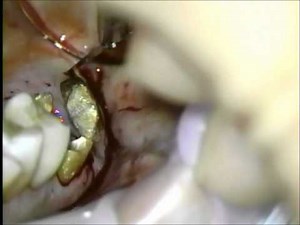

歯冠長延長術 Crown Lengthning Procedure

上顎大臼歯の歯冠長延長術 Crown lengthning procedure

視聴回数: 214 回

2015年1月20日